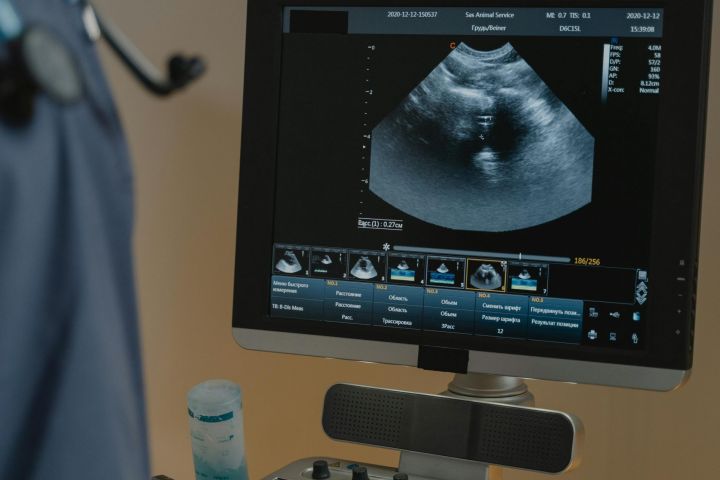

Infiltraciones guiadas por imagen

Ecografía, brazo en C y TAC

Para un tratamiento preciso y seguro, realizamos infiltraciones analgésicas guiadas por ecografía o rayos X (brazo en C), especialmente en articulaciones de la columna, raíces nerviosas o tendones profundos. Esto garantiza una colocación exacta del medicamento y mejores resultados terapéuticos.

Diagnóstico ortopédico por ecografía

Utilizamos ecografía para evaluar tendones, ligamentos, músculos y articulaciones en tiempo real, ayudando a diagnosticar desgarros, inflamaciones o acumulaciones de líquido sin radiación.